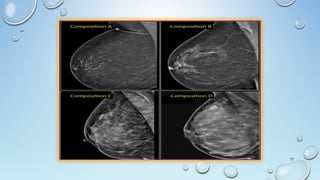

Breast Classifications

FIBRO-GLANDULAR BREAST

• Fibro-glandular

• Dense With Very Little Fat

• Females 15-30 Years Of Age

• Or 30 Years Or Older Without Children

• Pregnant Or Lactating

FIBRO-FATTY BREAST

• Fibro-fatty

• Average Density

• 50% Fat & 50% Fibro-glandular

• Women 30-50 Years Of Age

• Or Women With 3 Or More Children

FATTY BREAST

• Fatty

• Minimal Density

• Women 50 And Older

(Postmenopausal), Men And Children